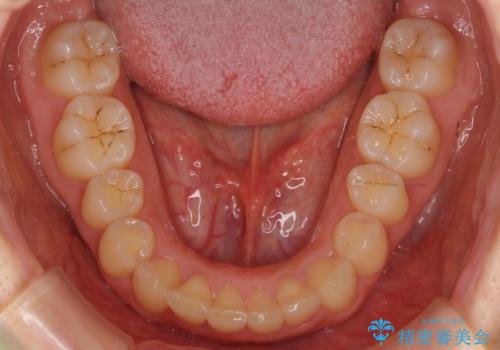

- 前歯のがたがたと出っ歯を主訴に来院。

CTを撮影したところ、臼歯部の頬側の骨の厚みが非常に大きく、通常では考えられない量の歯列の拡大が可能でした。

今回は健康を損なわずに非抜歯で治療が可能でしたが、

歯ぐきや骨の厚みが薄い他の患者さんでは難しいです。

左上5は180度捻転していましたので、そのまま並べています。

遠心移動などは行わず、IPRと拡大のみで治療を行いました。